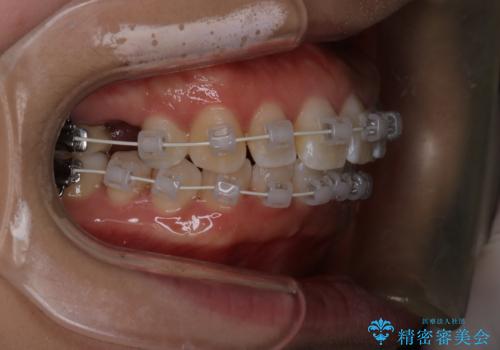

- 矯正装置

- 審美装置

- 上下前歯のがたつきを主訴に来院されました。

口元も下げたいということもあり、上2本抜歯を行い治療を行いました。

抜歯を行い、前歯のがたつき、前歯の出ているところを改善できました。

患者様の満足感も高く治療を終えられました。